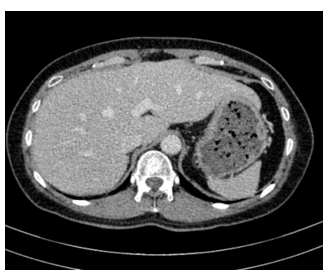

– Cắt lớp vi tính ổ bụng:

Hình 4: Hình ảnh cắt lớp vi tính ổ bụng có tiêm: chưa phát hiện tổn thương nghi ngờ thứ phát

– Cắt lớp vi tính ổ bụng: Không phát hiện tổn thương bất thường.